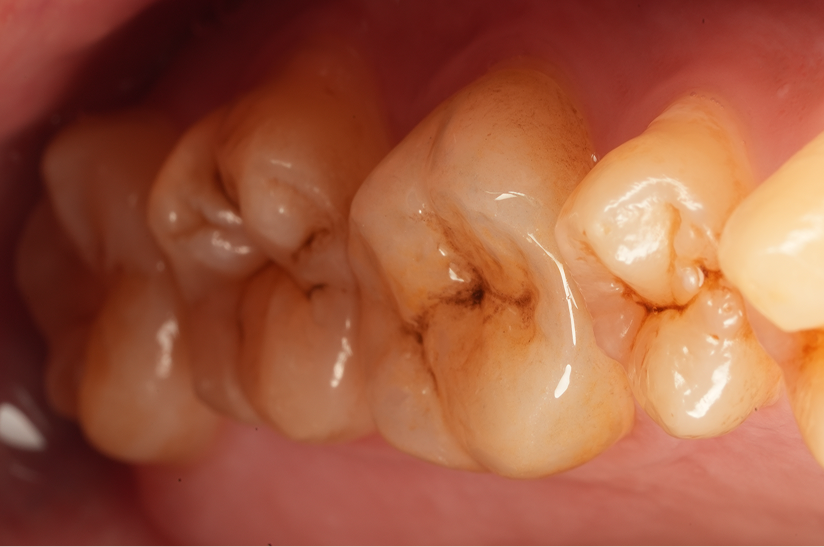

大臼歯の再根管治療を行った症例

タップで写真の拡大ができます。

Before&After(根管治療)

Before

Before&After(根管充填)

主訴

歯茎が腫れて、噛むと違和感がある

治療内容

再根管治療(大臼歯)

治療期間

1ヶ月

治療費用

165,000

治療の

リスク

処置中に歯肉縁下におよぶ重度のう蝕や破折を認めた場合、治療を中断する可能性があります。術後も症状が残る場合は追加の処置が必要になる可能性があります。